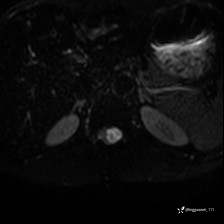

男,38岁,反复腰痛伴双腹股沟区痹痛半年,加重1月。

腰椎MR,注意脊髓异常信号,与伪影鉴别,一不小心就会漏诊

DWI ADC